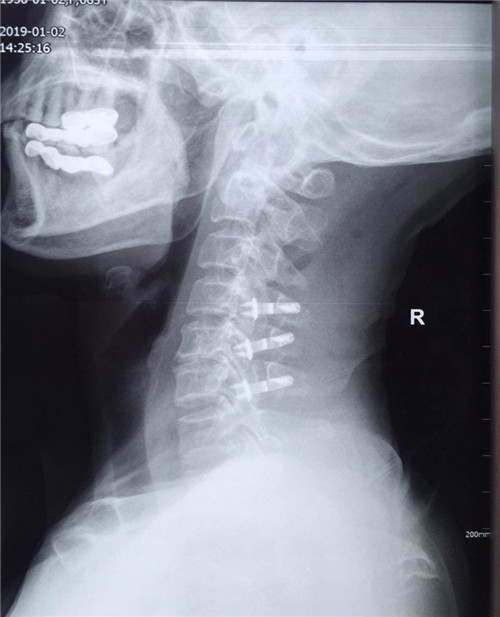

术后

患者入院后,骨一科医护人员为其做进一步检查,诊断为多发颈椎间盘突出并继发颈椎管狭窄症。经讨论研究后,程福宏副主任医师决定为其行颈后路颈4、5、6的单开门椎板扩大成形术,该手术在王小峰主治医师的配合下完成。术中,医生为患者进行彻底的减压脊髓,固定椎板。术后患者恢复较好,症状改善明显,已能够独自行走,恢复正常活动。